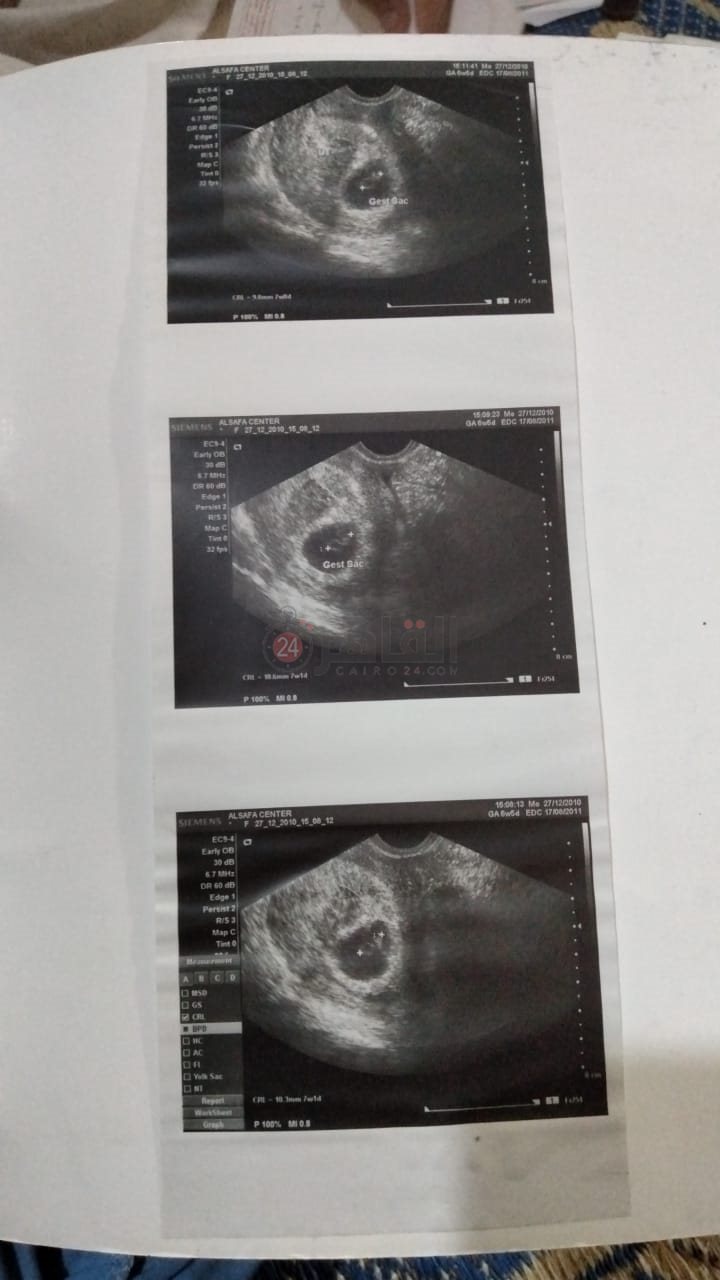

تروي تبارك عادل قصتها لـ القاهرة 24 قائلة: إنها تعاني من مرض الاستسقاء، ووجود مياه في البطن والحوض منذ 7 سنوات، حينما كان وزنها 65 كيلو تعرضت لحالة إعياء شديدة وإغماء على إثر ذلك تم نقلها إلى مستشفى بسيون المركزي وأثناء الكشف عليها ونقل دم لها، وبالصدفة لاحظت إحدى الطبيبات ورم بالمعدة، موضحة: «كنت مفكرة بطني وارمة بعد الولادة والناس مفكرة إني حامل، والدكتورة طالبتني بضرورة إجراء تحاليل شاملة وفحوصات طبيبة لتحديد المرض وتم تحويلي إلى مستشفى المنشاوي العام بطنطا».

كما أكدت تبارك عقب الفحص الطبي في مستشفى المنشاوي العام بطنطا تم تحويلها إلى معهد الأورام ثم عرضها على طبيب كبد ثم جامعة طنطا التي أجرت لها عدة مناظير ونخاع وعمليات لسحب المياه من البطن ثم مكثت عدة شهور داخل مستشفى الجامعة بطنطا دون تحسن أو الوصول إلى تشخيص الحالة ثم نقلها مرة أخرى إلى معهد الأورام بطنطا وأجريت عدة فحوصات طبية وأخذت منها عينات ومكثت 15 يوما.

فيما أشارت تبارك إلى أنها خلال رحلة علاجها بمعهد الأورام وفحصها تبين عدم إصابتها بأي أنواع ورم أو سرطان في الدم ثم عرضها على مستشفى المنصورة وإعطائها أدوية كورتيزون دون تحسن إلى أن توصل أطباء المستشفى أنها مصابة بمرض نادر.